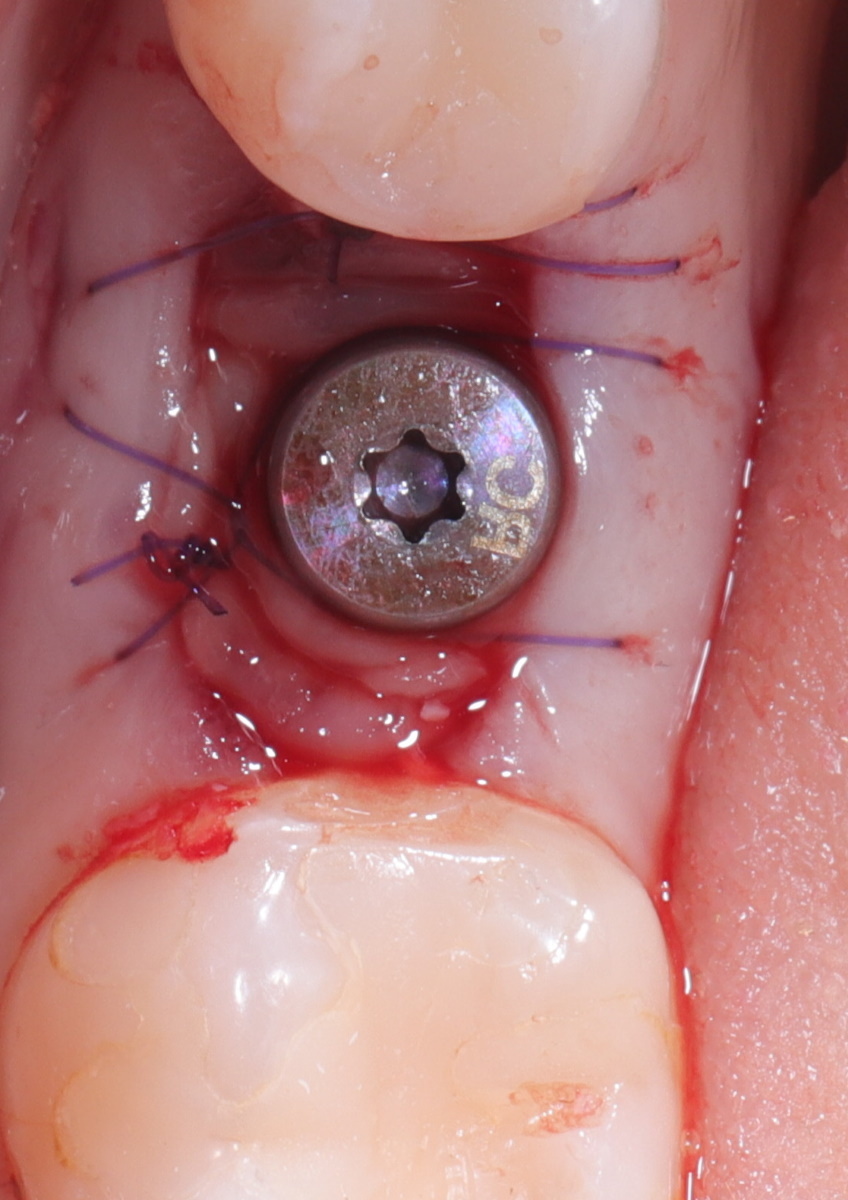

Имплант Straumann BLT 4.1*8mm SLActive - установлен в субкрестальное положение, произведено профилирование кортикальной кости системой Straumann Bone Profiler с целью создания более выгодного профиля прорезывания и исключения костной резорбции в области шейки импланта.

Чтобы компенсировать недостаточный объем мягких тканей проведена - мягкотканая пластика деэпителизированным соединительнотканным трансплантантом с неба.

Установлен заживляющий абатмент диаметром 6.5 мм.

Обратите внимание на объем и качество мягких тканей в области будущей финальной реставрации!